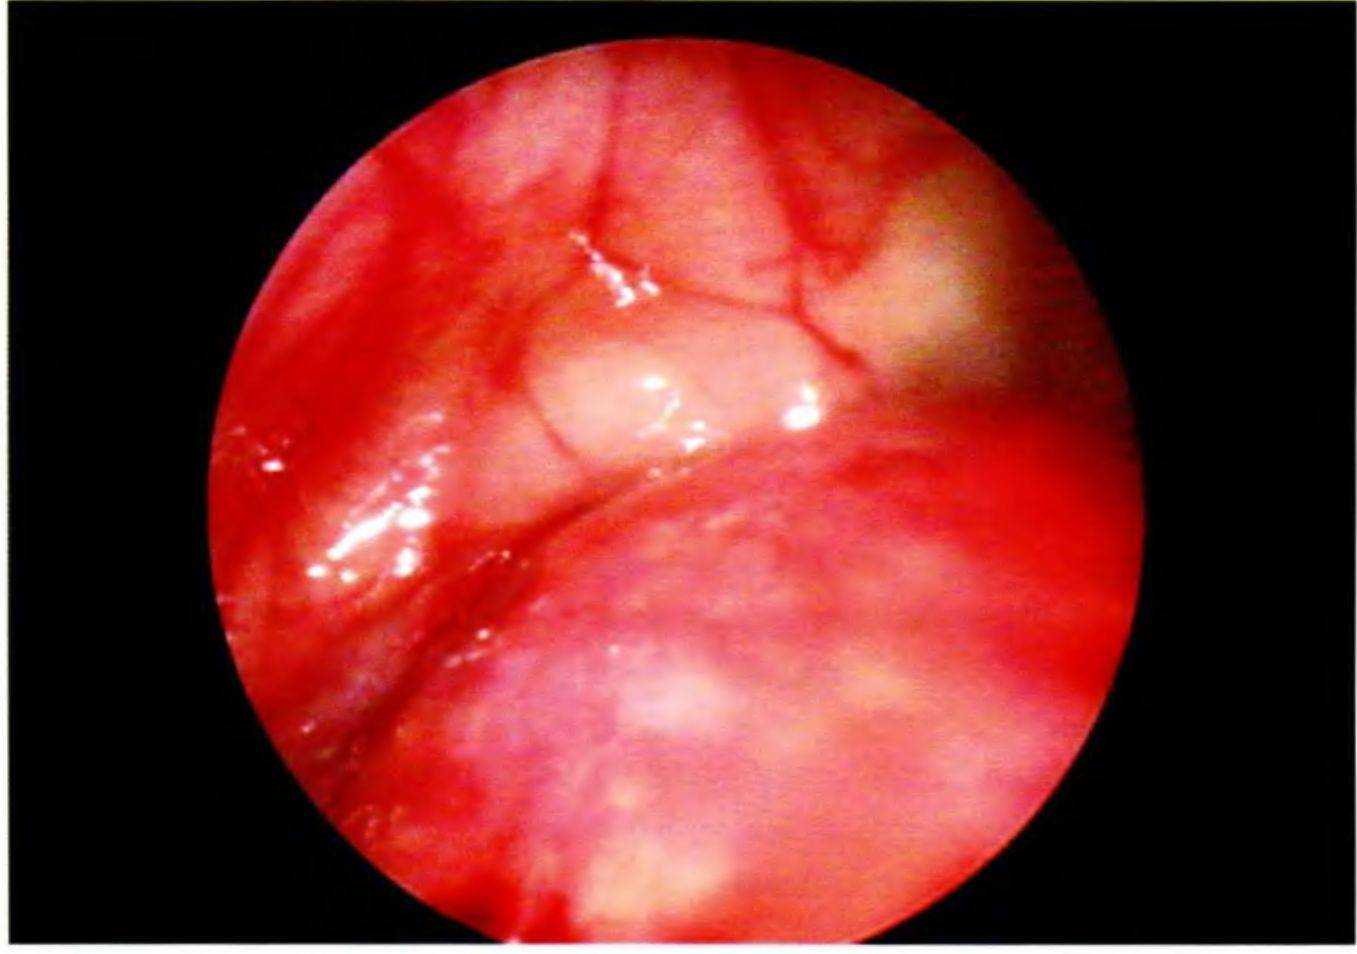

Лоскуты ушивают, например, нерезорбируемым шовным материалом ГорТекс CV-5 (GoreTex CV-5), и выполняют контрольную рентгенограмму. На рис. 5-23 продемонстрирован вид верхнечелюстной пазухи изнутри после закрытого синус-лифтинга одновременно с установкой имплантатов. Изображение получено с помощью оптоволоконного эндоскопа.

Рис. 5-23. Эндоскопическое исследование пазухи после синус-лифтинга и установки имплантатов (с разрешения проф. W. Engelke, Гёттингенский университет)